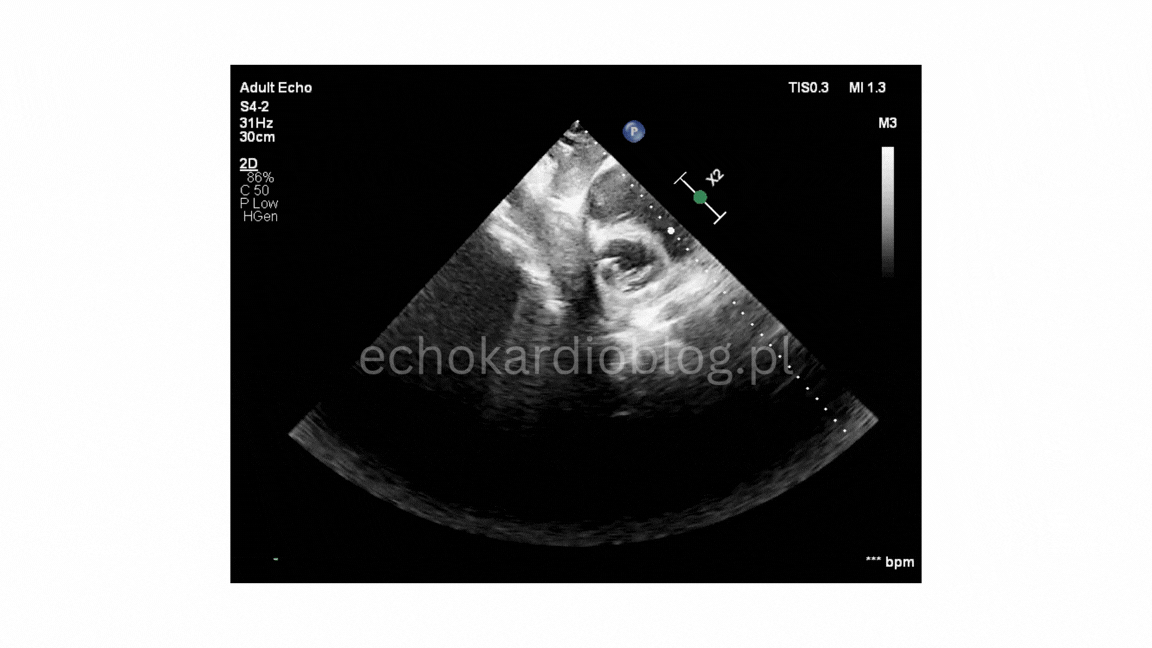

Pacjent , lat 66, przyjęty z podejrzeniem sepsy, w badaniu echokardiograficznym ujawniono duże, ruchome wegetacje na trzech zastawkach – mitralnej, trójdzielnej i płucnej . Wegetacje najlepiej widoczne były w projekcjach podmostkowych . Obraz jest dramatyczny: wysokie ryzyko powikłań zatorowych i przeciążenia prawego serca.

A 66-year-old patient admitted with suspected sepsis underwent echocardiography, revealing large, mobile vegetations on the mitral ,tricuspid and pulmonary valves .Vegetations were most clearly visualized in subcostal projections. The findings are dramatic, indicating a high risk of embolic complications and right heart overload.

wegetacja na płatku przednim zastawki mitralnej (segment A2) projekcja podmostkowa poprzeczna na zastawkę mitralną